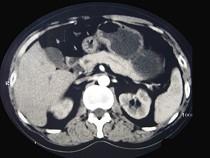

问题 男性,57岁,1年前无明显诱因反复出现嗜睡及发作性神志不清,进食糖水或甜品后症状即缓解,腹部CT检查如下图,最佳的诊断是()

选项 A.胰腺癌 B.胰岛细胞瘤 C.胰腺转移瘤 D.胃泌素瘤 E.舒血管活性肽瘤

答案 B